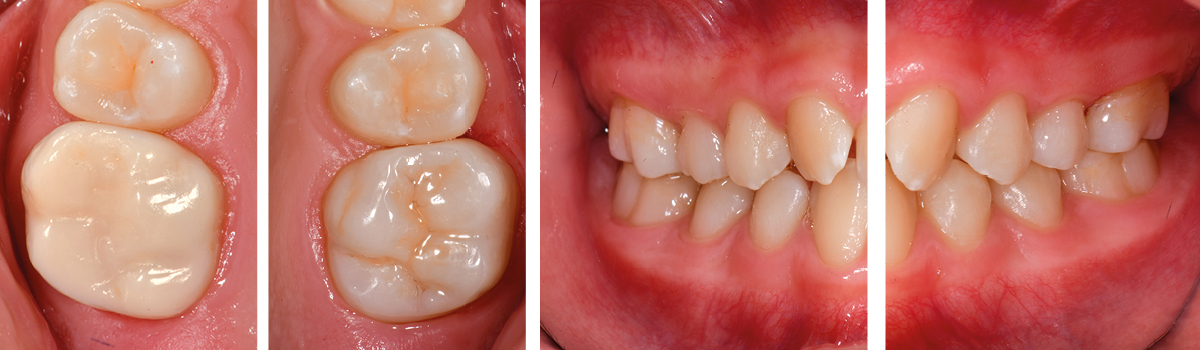

1. Initial findings of teeth 16 and 26. Due to the circular defect extension and hypersensitivity (MIH Treatment-Need-Index Score 4c), both teeth were restored with fullcrowns.

2. At the age of 11, the teeth had erupted so far that restoration margins could be prepared into sound enamel. A shoulder preparation of 1mm width was performed. Clinical situation before adhesive cementation procedure.

3. Situation after adhesive cementation of both crowns (16/26) - Occlusal view.